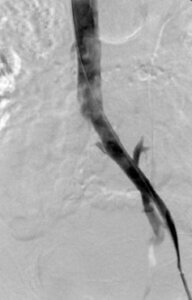

This image is from a venogram of the pelvis. It demonstrates narrowing of the left common iliac vein due to May-Thurner Syndrome with collateral vessels crossing the pelvis.

This image is from a venogram of the pelvis. It demonstrates narrowing of the left common iliac vein due to May-Thurner Syndrome with collateral vessels crossing the pelvis.